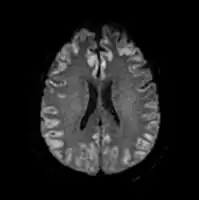

Acute severe hepatic encephalopathy -

Acute severe hepatic encephalopathy

The diagnosis of hepatic encephalopathy is a clinical one, once other causes for confusion or coma have been excluded; no test fully diagnoses or excludes it. Serum ammonia levels are elevated in 90% of people, but not all hyperammonaemia (high ammonia levels in the blood) is associated with encephalopathy.[3][8] A CT scan of the brain usually shows no abnormality except in stage IV encephalopathy, when brain swelling (cerebral oedema) may be visible.[8] Other neuroimaging modalities, such as magnetic resonance imaging (MRI), are not currently regarded as useful, although they may show abnormalities.[14] Electroencephalography shows no clear abnormalities in stage 0, even if minimal HE is present; in stages I, II and III there are triphasic waves over the frontal lobes that oscillate at 5 Hz, and in stage IV there is slow delta wave activity.[3] However, the changes in EEG are not typical enough to be useful in distinguishing hepatic encephalopathy from other conditions.[14]